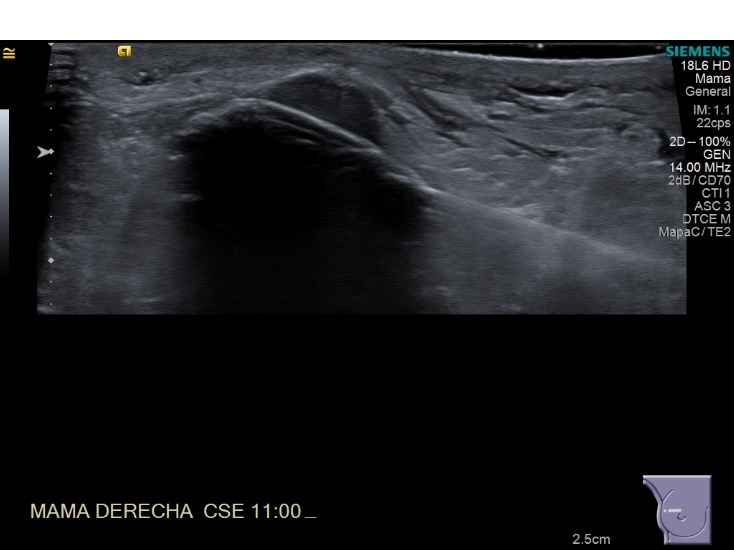

Crioablacion de tumor en mama derecha